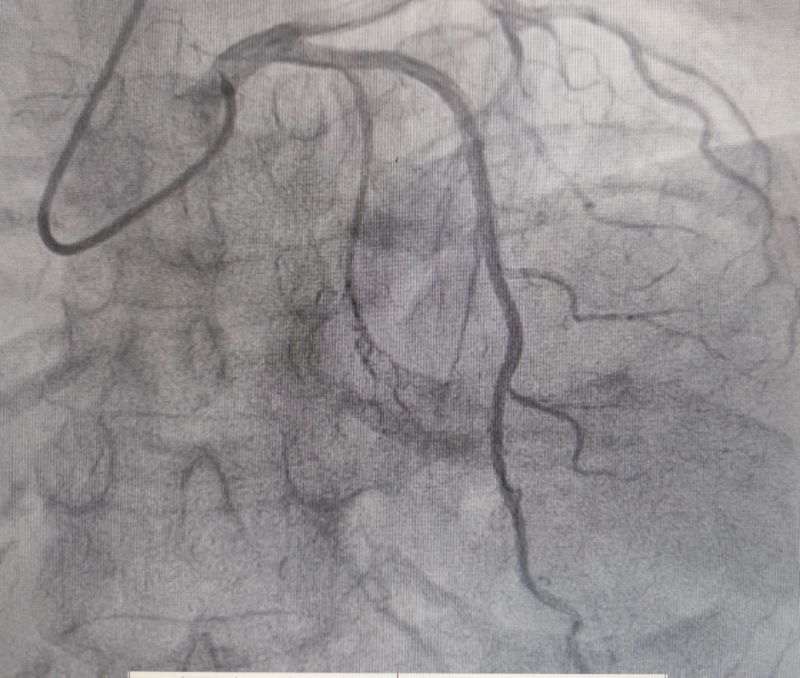

經過多輪嚴謹的術前討論,在吳棟梁院長的專業指導下,崔旭輝主任醫師團隊決定在臨時起搏器的安全保護下,為患者實施冠狀動脈造影術及室間隔化學消融術。術中,團隊通過造影精準鎖定第一穿隔支為消融靶血管。測壓數據顯示:左室壓260/15mmHg,流出道173/6mmHg,主動脈壓106/70 mmHg,壓力階差達87mmHg。隨后,團隊使用2.0X15mm預擴球囊以8atm壓力阻斷第一穿隔支遠端血流1分鐘,再次測壓時,壓力從269/7mmHg驟降至174/4mmHg,這一結果充分證實該血管正是室間隔的有效供血血管。緊接著,團隊通過SPRINTER OTW2.0×8mm球囊緩慢注入1.4ml無水酒精。10分鐘后復測,左心室壓降至136/5 mmHg,主動脈壓為112/93 mmHg。術后第2天,王女士胸悶、氣短、心悸等不適癥狀完全消失。復查心臟彩超顯示:EF值與FS值保持穩定,收縮期左室流出道血流速度降至252cm/s,PG值為25mmHg。

消融后造影